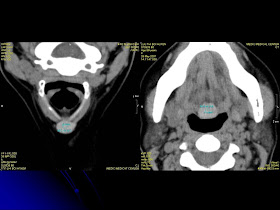

A 50 yo female patient was detected randomly with a small nodule at the base of her tongue per ENT endoscopy. This nodule does not appear on neck ultrasound but an another mass was found at hyoid region by ultrasound: solid, echo poor, well vascularization, and no thyroid gland detected at the normal site. At last, on MDCT 64, the 2 ectopic thyroid focals were revealed, one at the base of the tongue and the other, at thyrohyoid membrane.